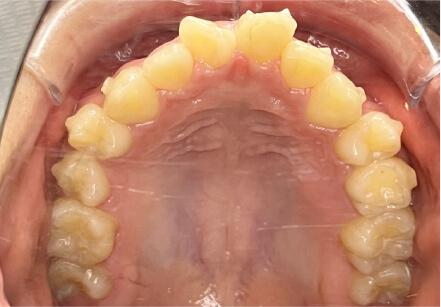

叢生の症例

10歳

女性

相談内容

スペース不足

カウンセリング・診断結果

myoからの移行。スペース不足のためインビザライン開始。

治療内容・方法

全額アライナー矯正

術後の経過・現在の様子

クリアライナー使用

治療のリスク

痛み・歯根吸収・歯肉退縮・虫歯・後戻り

費用・治療期間

(インビザのみ)385,000円、1年2ヶ月 + myo3年4ヶ月